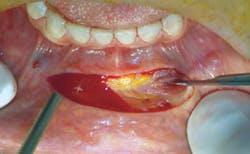

mucosal incision There is no argument that recent innovations in the diagnosis and management of disease involve the application of technology. However, can some of the complementary technological advancements and gadgets that have become lifestyle necessities actually cause disease themselves? Blackberry thumb, iPad finger, and tech neck are becoming the common new ailments compromising our work, activities of daily living, and perhaps even our appearance. Smartphone face is the phenomenon that describes how sitting for hours with your head tipped forward staring at a smartphone, laptop or computer screen, will shorten the neck muscles and increase gravitational pull on the lower face and chin. This leads to submental fullness, double chin (buccula), facial sagging (jowls) and a recessive chin profile (microgenia). The development of the symptoms characterizing smartphone face can be attributed to genetics, the natural aging process and weight fluctuation; nevertheless, the explosion in the use of electronic gadgets has mirrored the rise in individuals seeking treatment of the chin. According to the American Society of Plastic Surgeons the number of chin augmentation surgeries performed in the United States increased over 70 percent in 2011. This increase is more than breast augmentation, botox and liposuction. With equal numbers of both men and women opting for the procedure, it makes chin augmentation the fastest growing plastic surgery trend. A trend that is expected to continue as facial aging may first appear in the chin and jaw line. The posting of pictures on Facebook and Instagram and the increasing prevalence of video chat technology, like Skype and FaceTime where perceived flaws are instantly captured for all to see, may be driving force behind the escalating numbers. Many people are seeking ways to improve their appearance, boost self-confidence and provide themselves any competitive advantage in the workplace.Click here to read the entire article.This article and photo originally appeared in the August 2013 issue of Oral Health and are with permission.